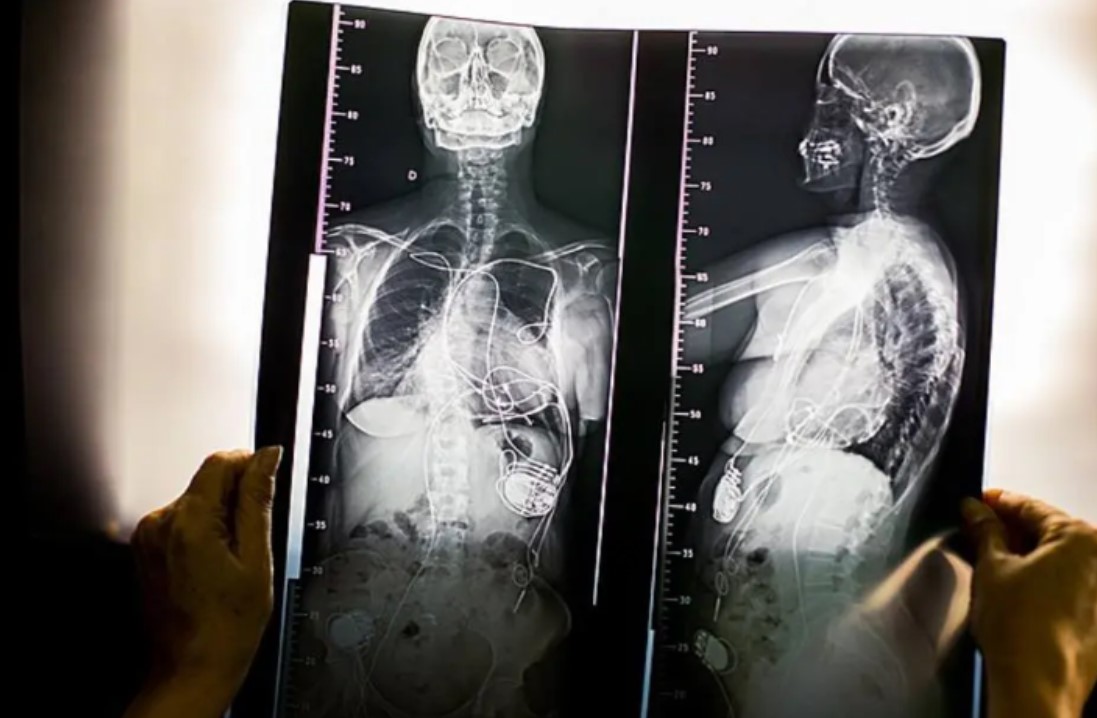

O raio X do tórax de Ana Mafalda de Almeida Fernandes Goulão Corrêa mostra um conjunto de fios entrelaçados ao redor do seu coração. No peito da aposentada está, há 55 anos, parte da história do marca-passo, dispositivo que regula o ritmo cardíaco com estímulos elétricos.

Ela vai ter de trocar o ressincronizador até janeiro. Assim como ocorreu das outras vezes, os eletrodos dos antigos procedimentos serão mantidos. “Esses fios estão lá dentro. Para mexer nisso, teriam de abrir o coração.” Ela não demonstra preocupação com o procedimento. “Vivo uma vida normal, vivo um dia de cada vez. Quem dirige a minha vida é Deus.”